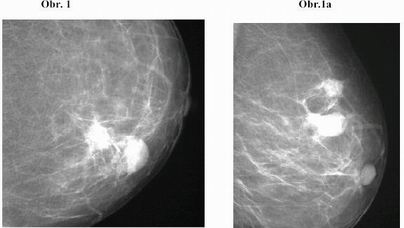

1. Pacientka A.P., 62 let.Mammografický obraz doložen na

Obr. 1, Obr. 1a.

Evidentní karcinom v ZHK levé mammy, v jeho okolí denzní opacita

bez obsahu mikrokalcifikací- hematom. Nápadné oploštění komplexu

bradavka – dvorec. Histologicky: pT1c pN1b M0, invazivní lobulární

karcinom, Grade 2, Estrogenní receptory 58%, progesteronové

receptory 40%, ki67 15%, Her2 +. V okrajích vzniklého hematomu DCIS

+ LCIS + invazivní lobulární karcinom.

V tomto případě byla jednoznačně indikace mammotomie - pokročilý

karcinom mléčné žlázy.

Otázkou je stanovení T klasifikace karcinomu, nebylo známo, jaká

porce karcinomu byla odstraněna mammotomií.